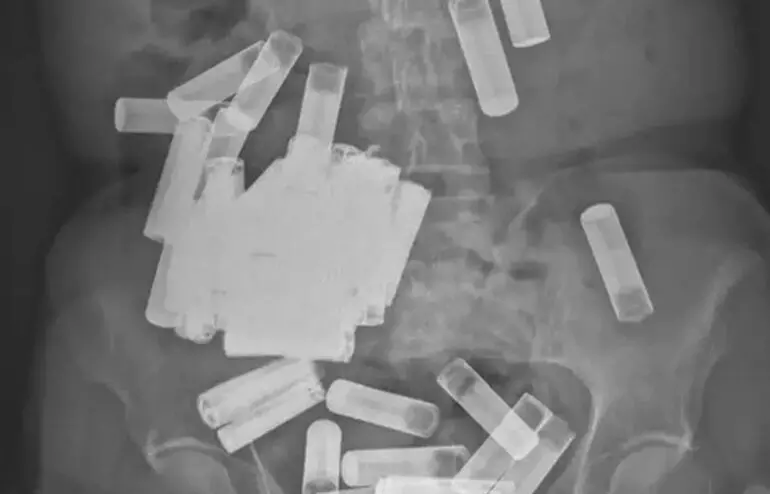

66കാരിയുടെ വയറ്റിൽ നിന്നും നീക്കം ചെയ്തത് 55 ബാറ്ററികൾ; അമ്പരന്ന് ഡോക്ടർമാർ

text_fieldsഅയർലണ്ടിൽ വയറുവേദനക്ക് ചികിത്സതേടിയെത്തിയ 66 കാരിയുടെ എക്സറെ കണ്ട ഡോക്ടർമാർ അക്ഷരാർഥത്തിൽ ഞെട്ടി. ഒരു കൂട്ടം ബാറ്ററികളാണ് ഇവരുടെ വയറ്റിലുണ്ടായിരുന്നത്. 55 ബാറ്ററികളാണ് വയറ്റിൽ നിന്നും ഡോക്ടർമാർ നീക്കം ചെയ്തത്. സ്വയം അപകടപ്പെടുത്തുന്നതിനായാണ് ഇവർ ബാറ്ററി വിഴുങ്ങിയത്. ബാറ്ററികളുടെ ഭാരം കാരണം ആമാശയം പ്യൂബിക് എല്ലിന് മുകളിലേക്ക് തൂങ്ങിക്കിടക്കുന്ന നിലയിലായിരുന്നെന്ന് ഡോക്ടർമാർ പറഞ്ഞു.

ആദ്യം ബാറ്ററികൾ മലത്തിലൂടെ പുറത്തുപോവുമെന്നാണ് ഡോക്ടർമാർ കരുതിയിരുന്നത്. നാലു ബാറ്ററികൾ ഇത്തരത്തിൽ പോവുകയും ചെയ്തു. എന്നാൽ മൂന്നാഴ്ചകൾക്ക് ശേഷം എടുത്ത എക്സ്റെയിൽ ബാറ്ററികൾ കുടുങ്ങിക്കിടക്കുന്നതായി കണ്ടു. അപ്പോഴേക്കും ഇവർക്ക് കലശലായ വയറുവേദന അനുഭവപ്പെട്ട് തുടങ്ങിയിരുന്നു.

ഇതിനെതുടർന്ന് വയറ്റിൽ ദ്വാരമുണ്ടാക്കി 46 ബാറ്ററികൾ നീക്കം ചെയ്യുകയായിരുന്നു. പിന്നീട് വൻകുടലിൽ കുടുങ്ങിയ നാലു ബാറ്ററികളും നീക്കം ചെയ്തു. ഐറിഷ് മെഡിക്കൽ ജേർണലിൽ നിന്നുള്ള വിവരങ്ങളനുസരിച്ച് ഡബ്ലിനിലെ സെന്റ് വിൻസെന്റ് യൂണിവേഴ്സിറ്റി ഹോസ്പിറ്റലിൽ ചികിത്സയിലാണ് ഇവർ.

66കാരിയുടെ വയറ്റിൽ നിന്നും ആകെ 55 ബാറ്ററികൾ നീക്കം ചെയ്തതായി ജേർണലിൽ പറയുന്നു. ലോകത്ത് റിപ്പോർട്ട് ചെയ്തവയിൽ ഏറ്റവും ഉയർന്ന എണ്ണമാണിത്. വയറ്റിൽ നിന്നും നീക്കം ചെയ്ത ബാറ്ററികൾക്ക് ഘടനാപരമായ മാറ്റങ്ങളൊന്നും ഉണ്ടായിട്ടില്ലെന്നും ഡോക്ടർമാർ വ്യക്തമാക്കി.